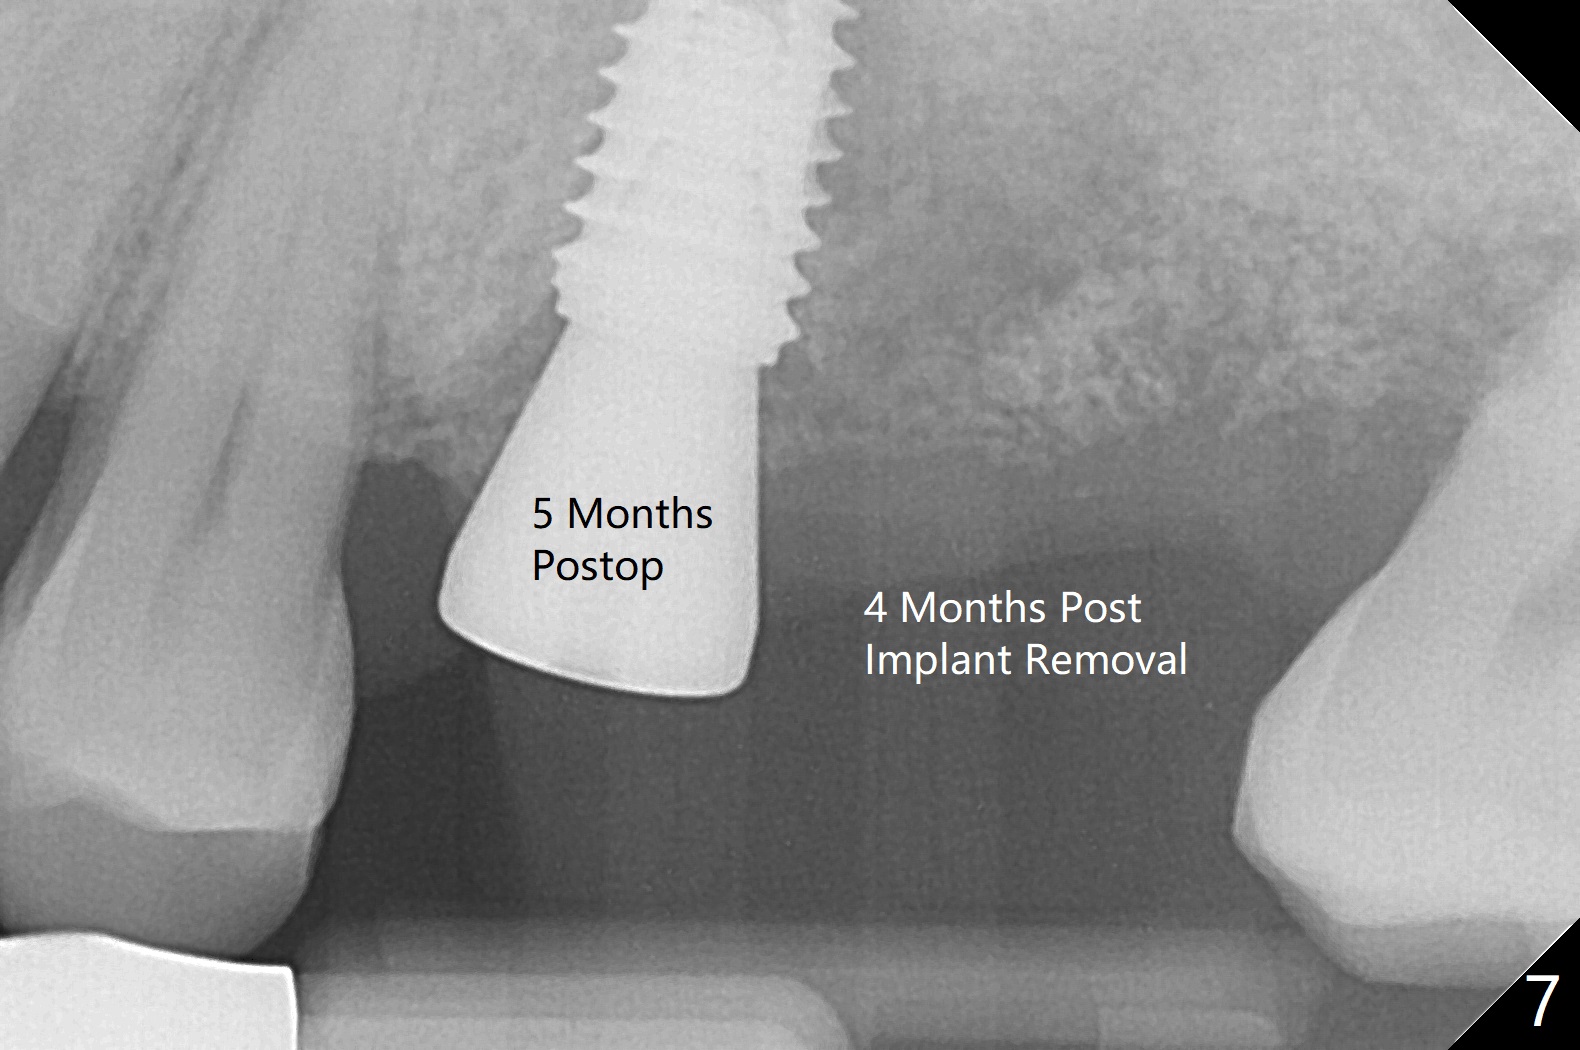

Six days later, "pain is less". Percussion of #13 healing abutment causes headache. There is no mobility at #13 or 14. The buccal gingiva is severely erythematous and edematous at #14. Chlorhexidine irrigation is conducted. After removal of the slightly subgingival healing abutment without pain, a 6x7 mm one is placed with severe pain. After local anesthesia, the implant seems to be mobile. The new abutment is advanced ~ 1 mm (Fig.5). Augmentin is prescribed. One week later there is no sign or symptom of infection. It appears that Augmentin should be prescribed after sinus surgery. The implant at #14 is removed with bone graft 1 month post placement. The graft appears to heal 4 months post implant placement (Fig.6,7 (5 months post placement at #13)).